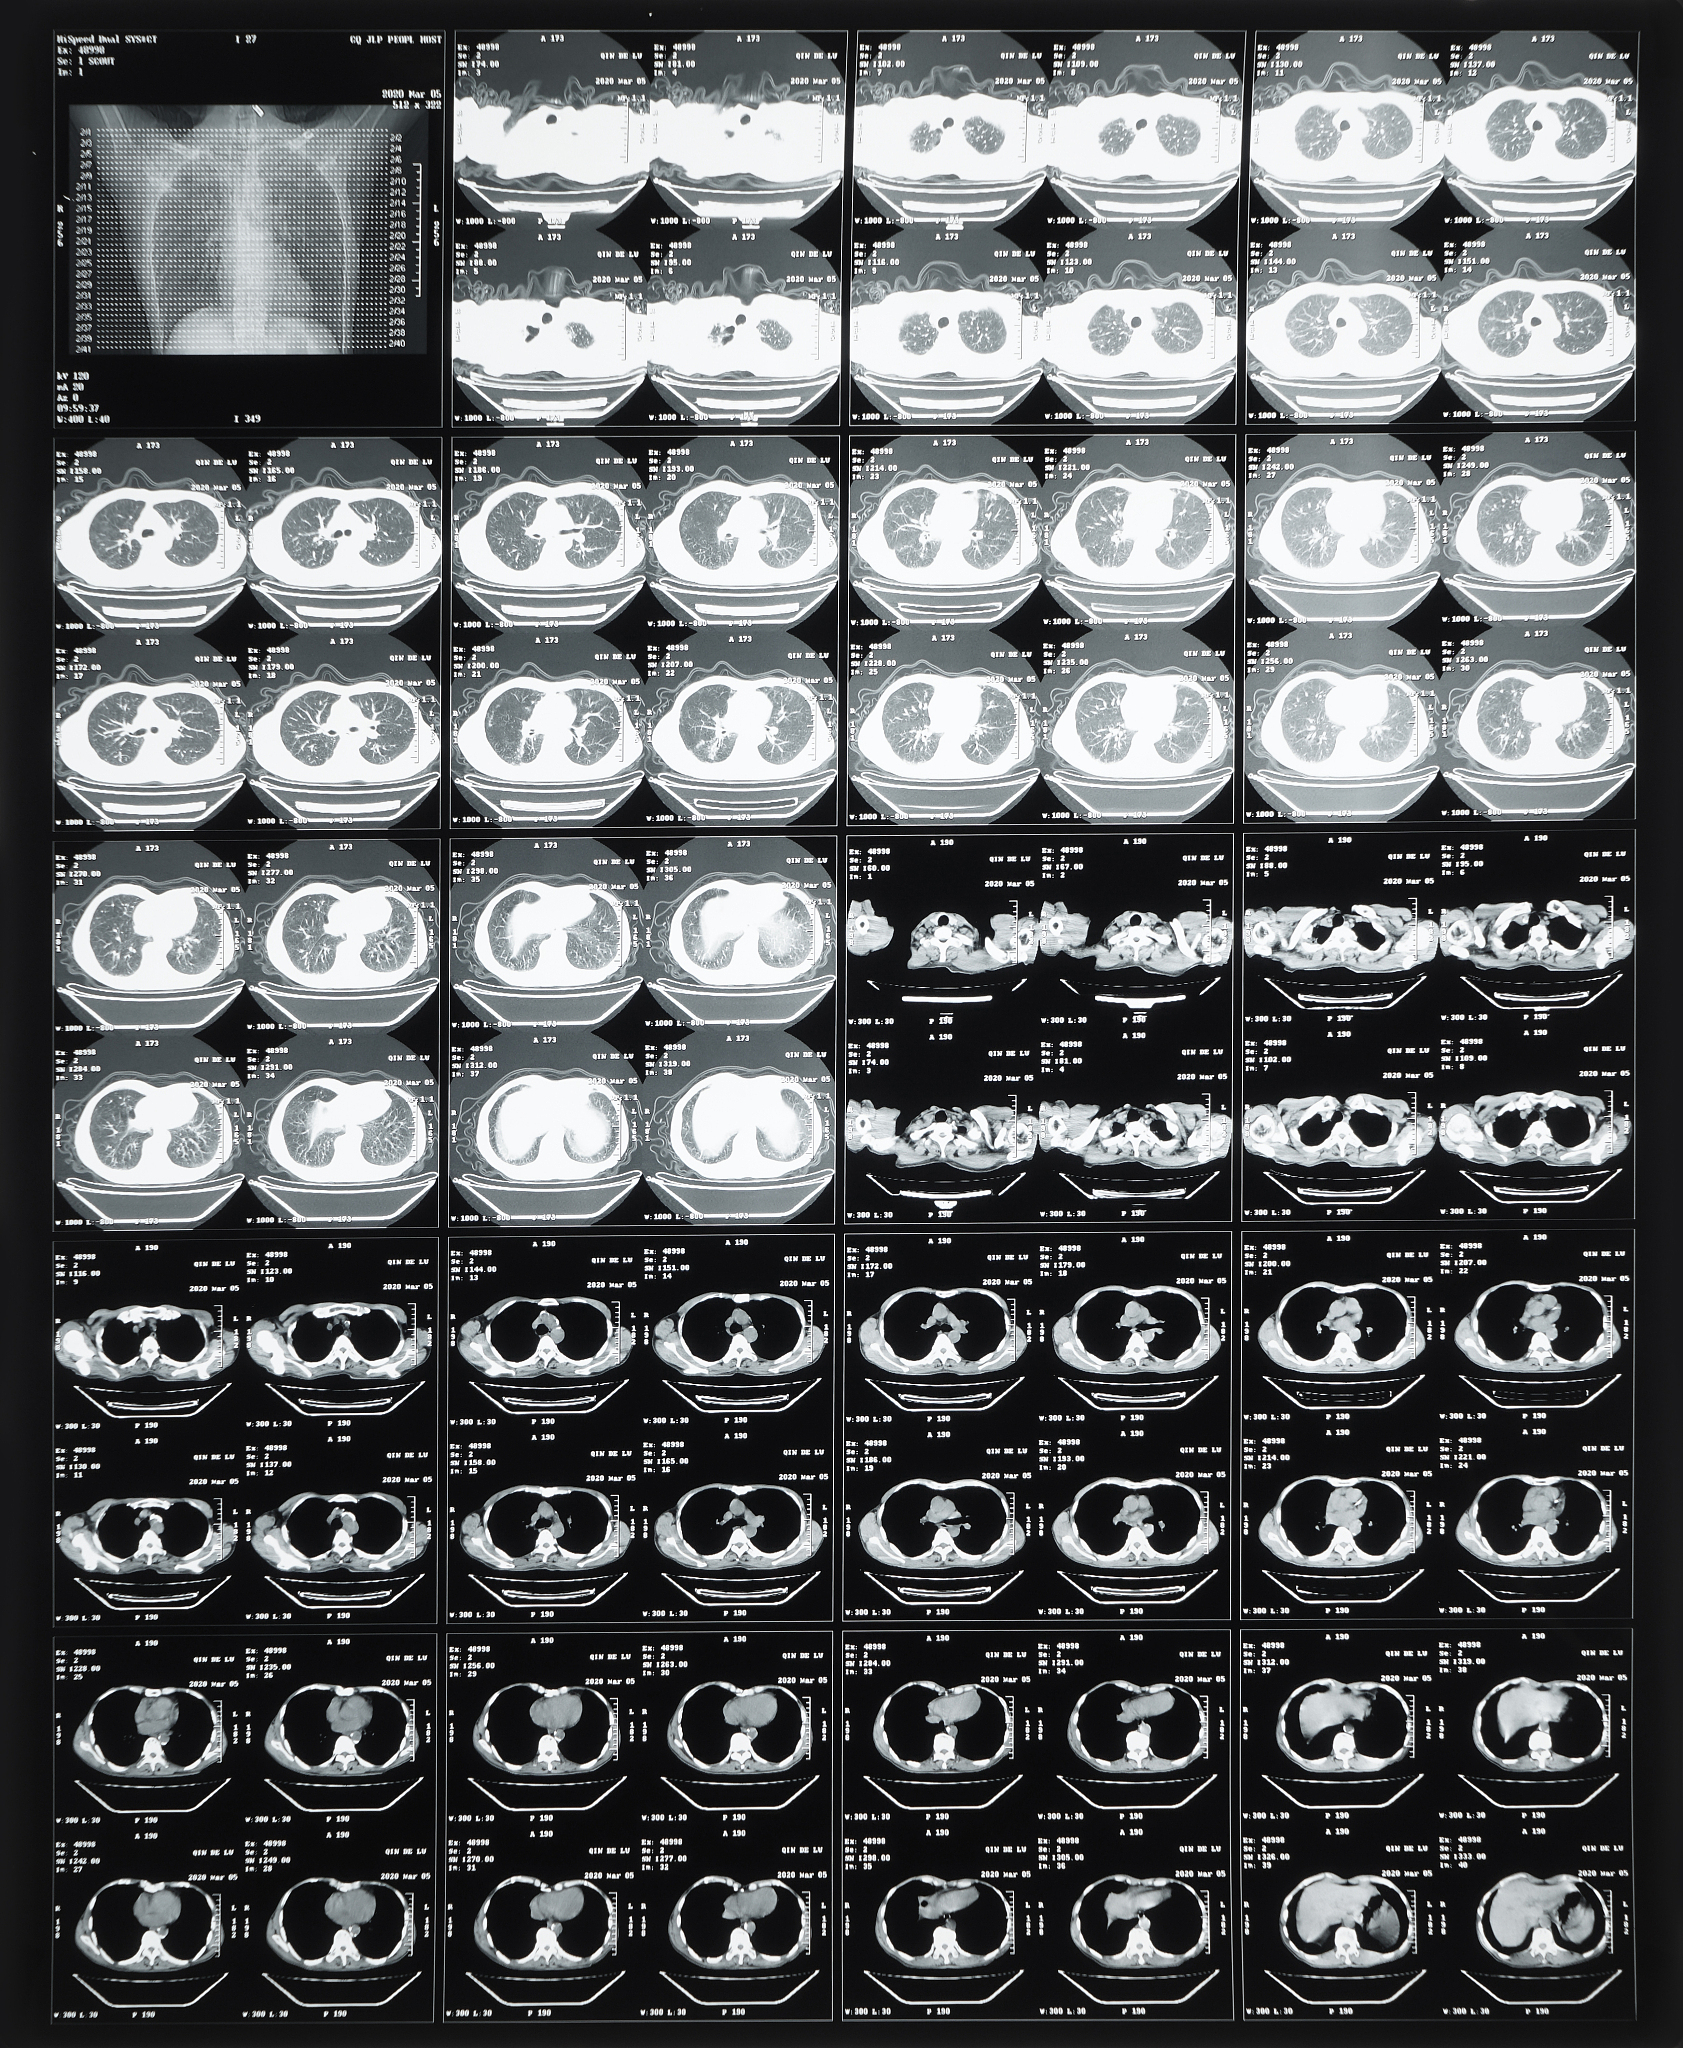

影像学检查是诊断胸腰椎管内多发神经鞘瘤的主要手段,其中MRI(磁共振成像)能够提供高分辨率的图像,清晰显示病变的位置、数量和大小。此外,组织活检也是确诊的重要手段,通过病理学分析可以确定病变的类型和恶性程度。